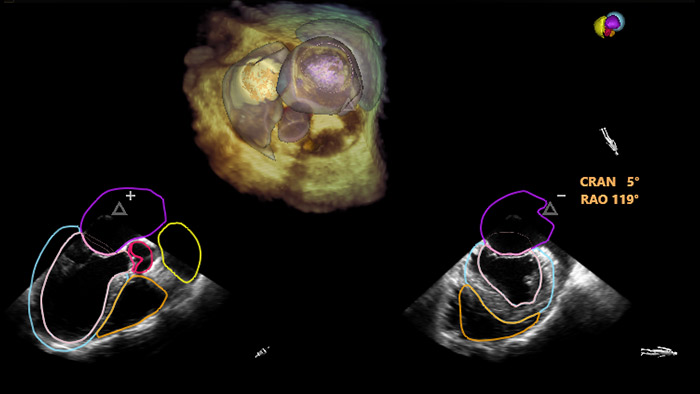

En el centro de nuestra suite, la exclusiva solución EchoNavigator es el ejemplo emblemático del compromiso de Philips con la multimodalidad y la integración del flujo de trabajo, aporta lo mejor de ambos mundos del líder de la industria en soluciones cardíacas intervencionistas de rayos X y ecografía.

Implementación de la superposición de la ETE 3D en vivo de la oclusión de la LAA con EchoNavigator

Guía de punción transeptal mediante EchoNavigator